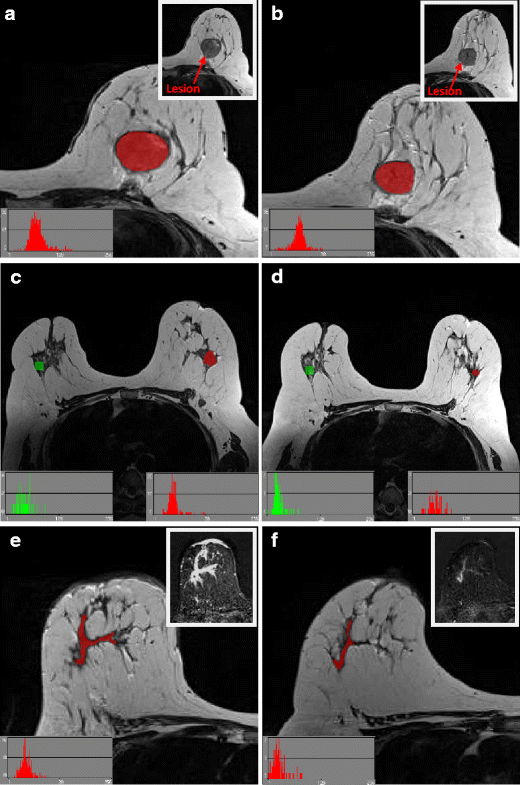

Region of interest (ROIs) (red) drawn for texture analysis on two patients, with slices matched between baseline (left column) and interim (right column) examinations. Insert images highlight lesion locations without ROI overlay. Image (a) and (b) are from slice-matched T2-weighted images from a woman who had a RCB-III at final pathology, while (c) and (d) are from slice-matched images in a patient that ultimately achieved a pCR at end of treatment. Images (e) and (f) highlight the importance of correlation with the subtracted dynamic contrast-enhanced imaging (DCE) images, particularly in the case of non-mass enhancement, as shown

T2-weighted images were magnified to visualise the tumour border and an ROI drawn around the entire tumour on the imaging slice demonstrating maximum lesion diameter, with no marker clip present. Histograms were visualised to ensure no fat was erroneously present within the ROI (see Fig. 2). A 10 × 10 pixel ROI was placed in healthy, normal contralateral breast parenchyma to exclude systematic inter-scan differences (as shown in Fig. 2(c,d)). These were placed in comparable regions of breast parenchyma at baseline and interim to ensure consistency and care was taken to exclude presence of vessels within the ROI. Data was rescaled to 6 bits/pixel and the image histogram normalized to within 3 standard deviations of the mean to minimise brightness and contrast variations. Entropy features, representing heterogeneity, were derived from the grey-level co-occurrence matrix [33], as these are reported in the literature as most appropriate for cancer imaging [29]. Inter-pixel distances of n = 2 and n = 5 were calculated to depict fine and coarse texture. Raw feature values were exported for statistical analysis.